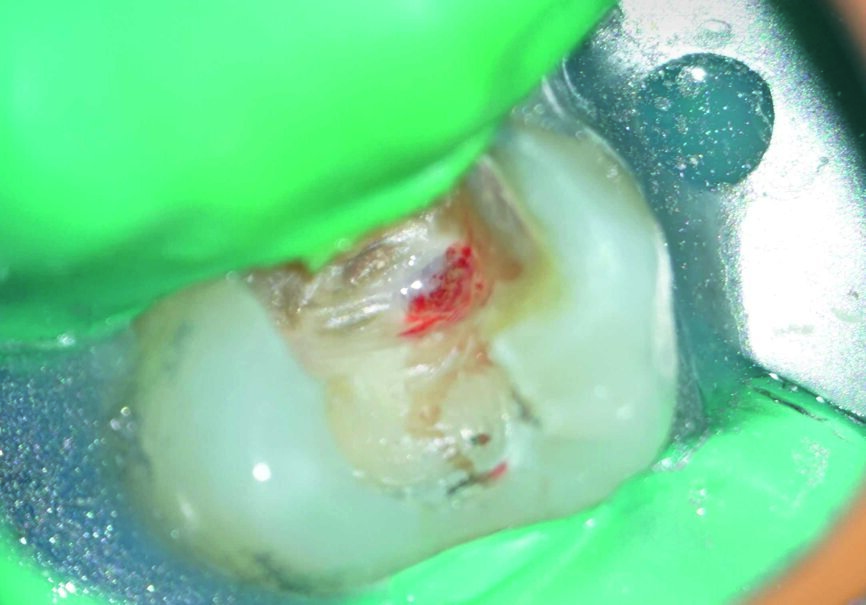

Ein 24-jähriger Patient kam mit vorübergehenden, provozierten Zahnschmerzen an Zahn #19 in die Zahnklinik (Abb. 1). Die Diagnose lautete reversible Pulpitis. Die Zahnfäule wurde unter kompletter Isolation entfernt, wobei es zweimal zur Freilegung der Pulpa mit minimalen Blutungen kam (Abb. 2). Die Blutungen wurden gestoppt, indem 10 Sekunden lang ein mit steriler Salzlösung getränkter Wattebausch auf die Stelle gedrückt wurde. Die Mundhöhle wurde mit 2,5% Natriumhypochlorit desinfiziert (Abb. 3), anschliessend wurde weißes MTA (Produits Dentaires) als Mittel zur unmittelbaren Pulpa-Überkappung eingesetzt (Abb. 4). Um sicherzustellen, dass das MTA korrekt eingesetzt wurde, kam das MAP-System für Dentalmaterialien (Produits Dentaires) zur Anwendung. Mit diesem System kann der Klinikarzt das Material exakt an der Expositionsstelle anbringen. Somit wird eine Verunreinigung der Dentinwände verhindert, die mit der Zeit eine Pigmentierung infolge des verwendeten Materials aufweisen könnten (Abb. 5 und 6). Sobald das MTA auf die Expositionsstellen der Pulpa und die tieferliegenden Teile des Pulpakammerdachs aufgetragen wurde, kam eine lichthärtende Kalziumhydroxidpaste zum Einsatz, um das Material zu schützen (Abb. 7), das Klebeverfahren durchführen und die abschliessende Zahnreparatur in derselben Sitzung vornehmen zu können (Abb. 8 und 9). Sieben Tage nach dem Verfahren war der Patient komplett symptomfrei und der Zahn reagierte normal auf Sensitivitätstests. In solchen klinischen Situationen ist davon auszugehen, dass zwischen sechs und neun Monaten nach dem Verfahren die Bildung von Kalkgewebe unter dem Überkappungsmaterial in Röntgenaufnahmen nachgewiesen werden kann. (7)